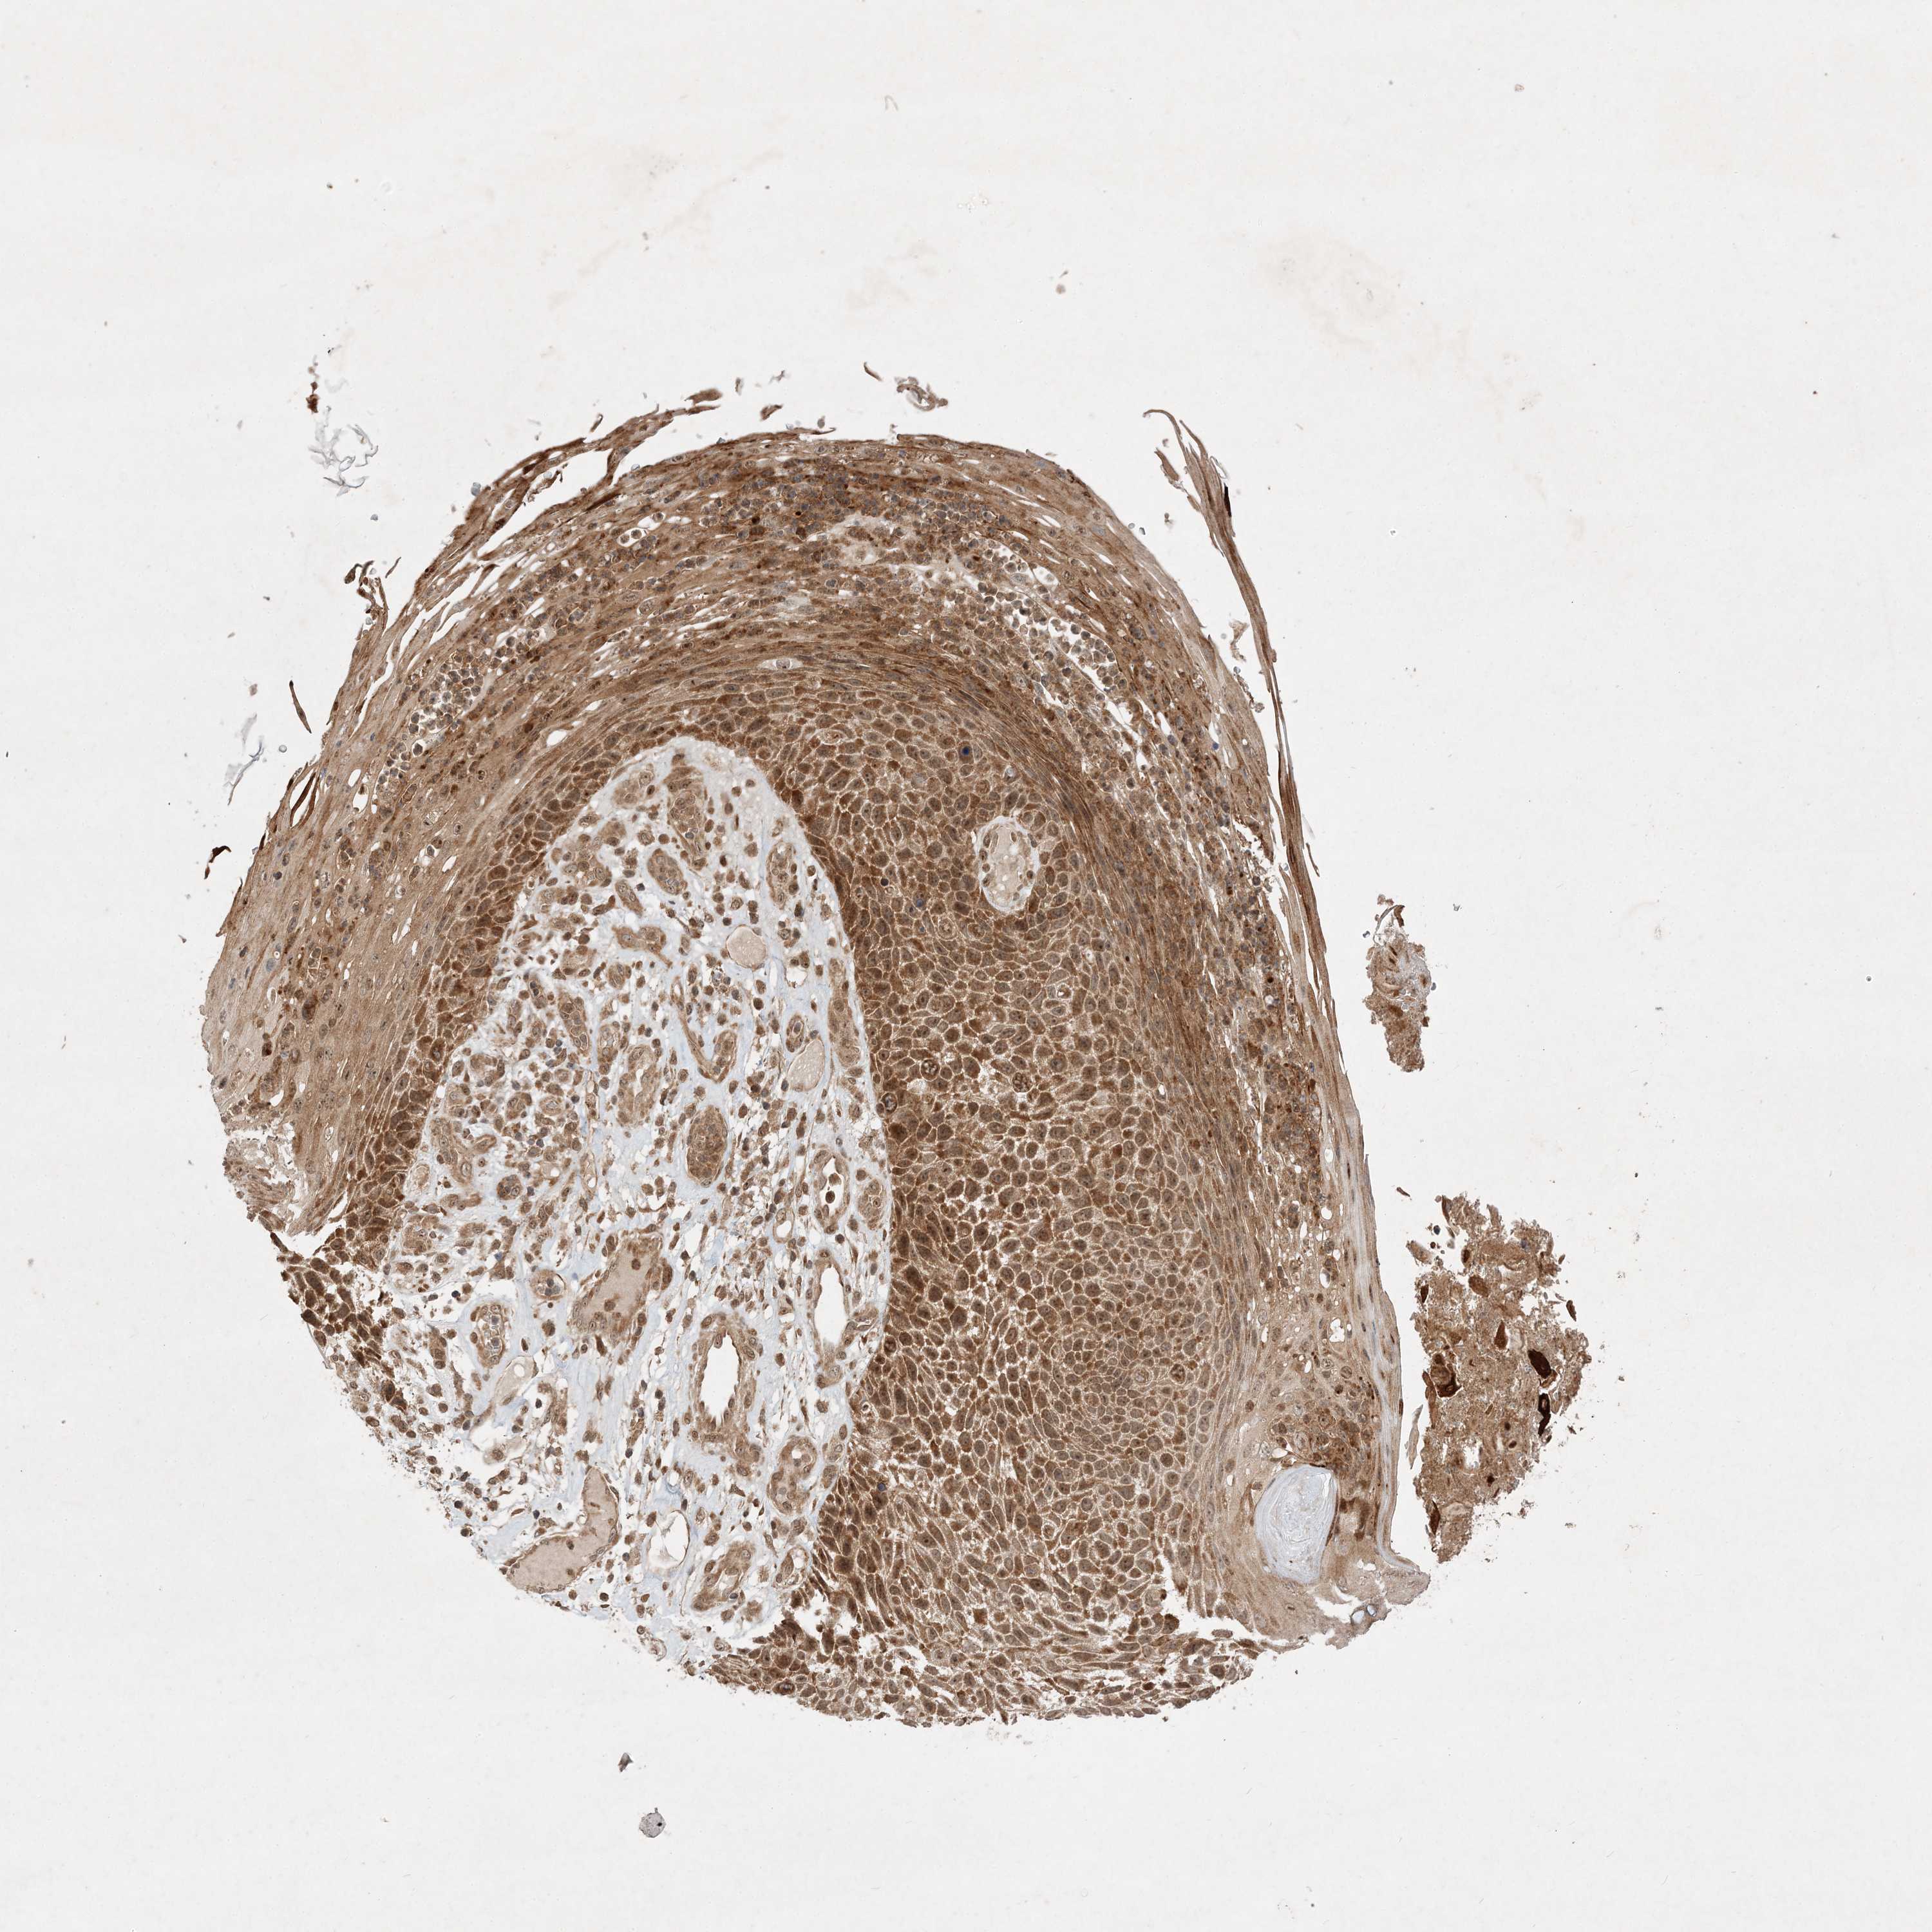

SKIN CANCER - Protein expressioni

A mouse-over function shows sample information and annotation data. Click on an image to view it in a full screen mode. Samples can be filtered based on level of antibody staining by selecting one or several of the following categories: high, medium, low and not detected. The assay and annotation is described here.

Antibody staining in the annotated cell types in the current human tissue is reported as not detected, low, medium, or high, based on conventional immunohistochemistry profiling in selected tissues. This score is based on the combination of the staining intensity and fraction of stained cells.

Each image is clickable and will lead to virtual microscopy that enables deeper exploration of all samples and also displays staining intensity scores, fraction scores and subcellular localization as well as patient and tissue information for each sample.

Antibody HPA035390

Basal cell carcinoma

Squamous cell carcinoma, NOS

Squamous cell carcinoma, metastatic, NOS